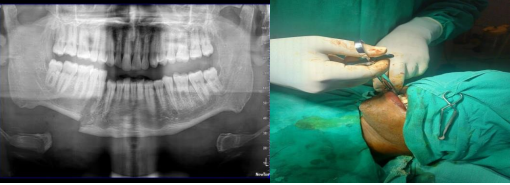

Figure 5.1 showing OPG of patient with right parasymphysis fracture undergoing ORIF under GA

Figure 5.2 showing inferior alveolar nerve block with 4% articaine post operatively by closed mouth (Vazirani-Akinosi) technique.

Figure 6.1 showing OPG of patient with left body fracture undergoing ORIF under GA

Figure 6.2 showing inferior alveolar nerve block with 0.5% bupivacaine post operatively by closed mouth (Vazirani-Akinosi) techniqu